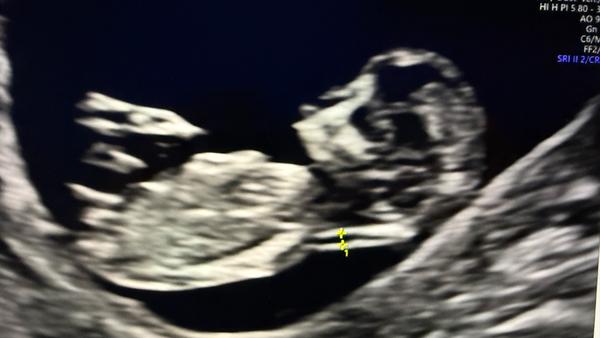

Může někdo určit pohlaví podle ultrazvuku ve 13+3 týdnu?

Nám dr v lednu rekla na 100%, ze holka... bylo to ve 14tt na 1.screeningu... mela fakt dobrý UZ. Ve 21tt to napsala do papírů z 2.screeningu.

@hollynka zdravím,nám tvrdili furt že to je holka a pak asi v 6-7 mesici se z toho nakonec vyklubal kluk😀 takze rikam dokud člověk neporodí neni si ničím jistý!😀